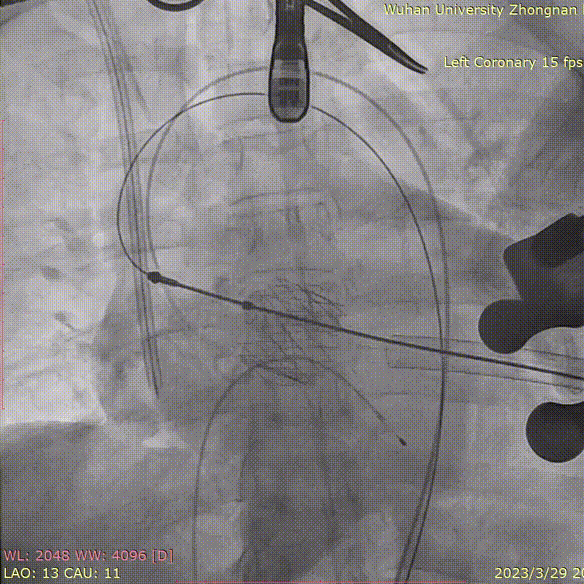

术中造影角度LAO 13°,CAU 11°;主动脉弓、降主动脉及双侧髂总动脉散在钙化,主动脉弓、腹主动脉局部管壁增厚,腹主动脉局部管壁不规则;升主动脉夹层、窦管交界增宽。

患者前降支中段重度狭窄,充分预扩后置入3.5*19mm支架一枚,复查造影提示支架膨胀良好,无明显残余狭窄。

猪尾放置于无冠窦行根部造影:

定位件于瓣环下打开,将瓣膜件降至合适平面,造影确认:

定位件入窦,造影:

调整导丝,使得瓣膜同轴:

再次造影确定位置:

释放瓣膜,复查根部造影,未见明显反流,瓣膜形态和位置满意,双侧冠脉未见遮挡征象: